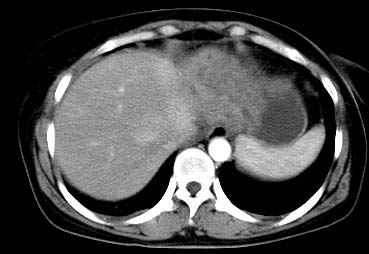

以下是引用西北一只狼在2008-6-30 20:58:00的发言:[br]肝左叶胆管细胞ca并肝门淋巴结转移、胰腺、胃小弯浸润

以下是引用ydx_74在2008-6-30 21:54:00的发言:[br]左叶胆管细胞ca并肝门淋巴结转移、胰腺、胃小弯浸润